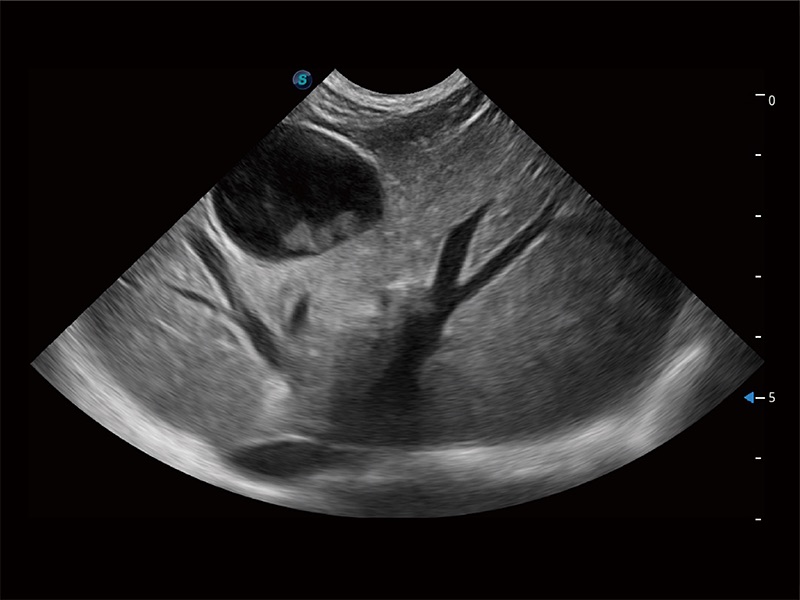

高性能和先進(jìn)的臨床應(yīng)用工具可以為動物醫(yī)生提供臨床信心。ProPet 80 搭載了先進(jìn)的腹部和淺表應(yīng)用工具,幫助醫(yī)生在日常臨床實(shí)踐中發(fā)揮前所未有的作用。

ProPet 80 配備了豐富的心臟探頭群、先進(jìn)的成像技術(shù)和專業(yè)的心臟測量工具,可幫助動物醫(yī)生為不同體型和生理結(jié)構(gòu)的動物提供心臟和心肌功能的全面評估。

ProPet 80 全新的動物超聲智能軟件和豐富的探頭群,為動物醫(yī)生提供了高清晰度和精細(xì)分辨率的圖像,無論在寵物、馬科、畜牧還是實(shí)驗(yàn)室動物等應(yīng)用中都可以輕松應(yīng)對,為您的日常工作帶來滿意的體驗(yàn)。